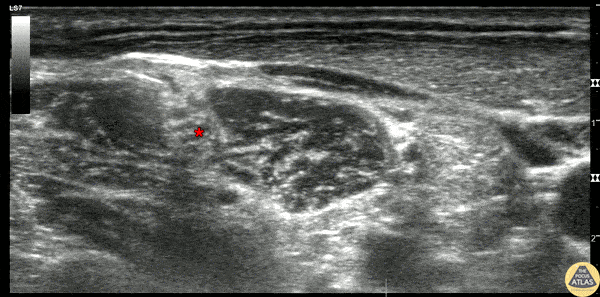

20s M with history of recurrent shoulder dislocation presented with shoulder pain and suspected dislocation. He was found to be neurovascularly intact, and after confirmation of dislocation with POCUS and XR, an interscalene nerve block was performed to facilitate reduction. The block is shown here, where the needle is seen entering from the posterior/lateral aspect at the left of screen, injecting anesthetic between the middle and anterior scalene muscles, adjacent to the brachial plexus nerve roots (*). The patient had relief of pain within minutes and was able to be reduced at the bedside without complication. Dr. Ian Eisenhauer, PGY-1 Denver Health Residency in Emergency Medicine